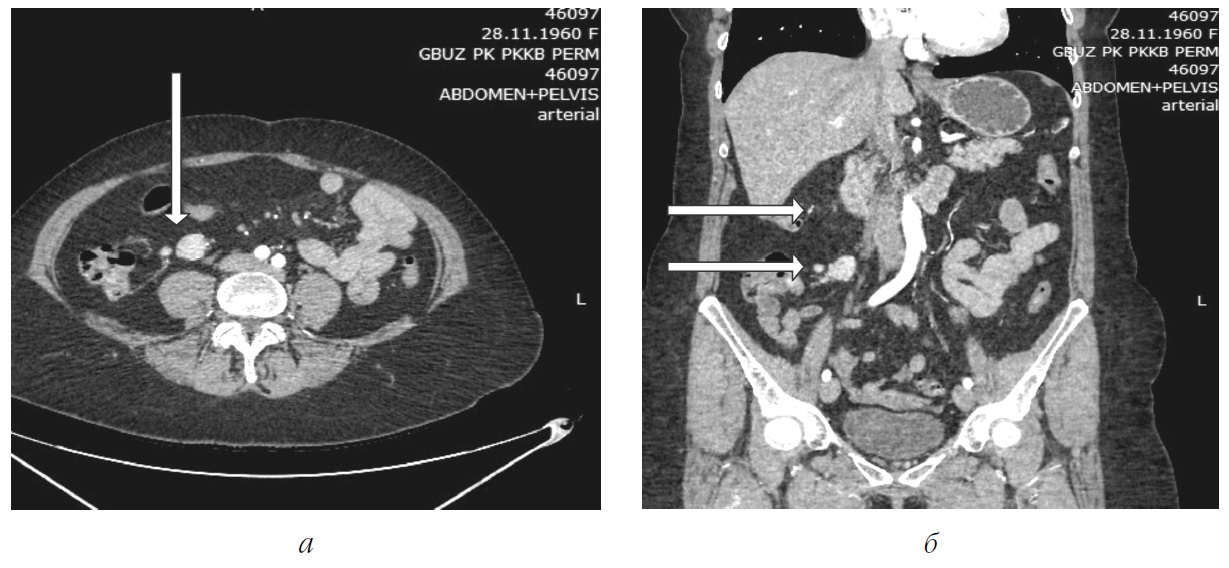

Через полгода на КТ с болюсным усилением от 06.05.2022 в терминальном отделе подвздошной кишки по брыжеечному краю обнаружено гиперваскулярное образование 9´15 мм, без четких контуров (рис. 1, а).

Рис. 1. Артериальная фаза. В терминальном отделе подвздошной кишки по брыжеечному краю определяется гиперваскулярное образование 9´15 мм без четких контуров: а – МСКТ-ангиография. Аксиальный срез; б – МСКТ-ангиография. Коронарный срез

По брыжейке тонкой кишки в области илеоцекального угла найдена группа увеличенных лимфатических узлов, самый крупных из которых имел размеры 25´18 мм (рис. 1, б).

В представленном случае клинические проявления заболевания были неспецифическими, а обследование начато с недостаточно информативного метода – МСКТ без болюсного контрастирования, что привело к задержке постановки правильного диагноза на 7 месяцев. Обнаружение увеличенного лимфатического узла в брыжейке тонкой кишки было неправильно интерпретировано, дополнительно проведено только эндоскопическое исследование желудка и толстой кишки. На низкую чувствительность МСКТ без болюсного усиления указывает A.K. Clift et al., поскольку НЭО тонкой кишки обычно имеют маленькие размеры [7]. При МСКТ-ангиографии удалось диагностировать не только конгломерат лимфатических узлов в брыжейке тонкой кишки, но и обнаружить опухоль размерами 9´15 мм в стенке подвздошной кишки. Наибольшую чувствительность МСКТ-ангиографии в выявлении НЭО тонкой кишки отмечают многие авторы с колебаниями от 50 до 85 % [3, 7, 8]. Обнаружение увеличенных лимфатических узлов в брыжейке тонкой кишки при этом методе обследования достигает более 94 % [3, 7, 8]. Эндоскопическое исследование желудочно-кишечного тракта с использованием баллонной или капсульной энтероскопии в сочетании с МСКТ-ангиографией обладает самой высокой чувствительностью в выявлении НЭО тонкой кишки [7]. Проведение лапароскопии с биопсией лимфатического узла после его морфологического исследования позволило нам верифицировать диагноз до операции.